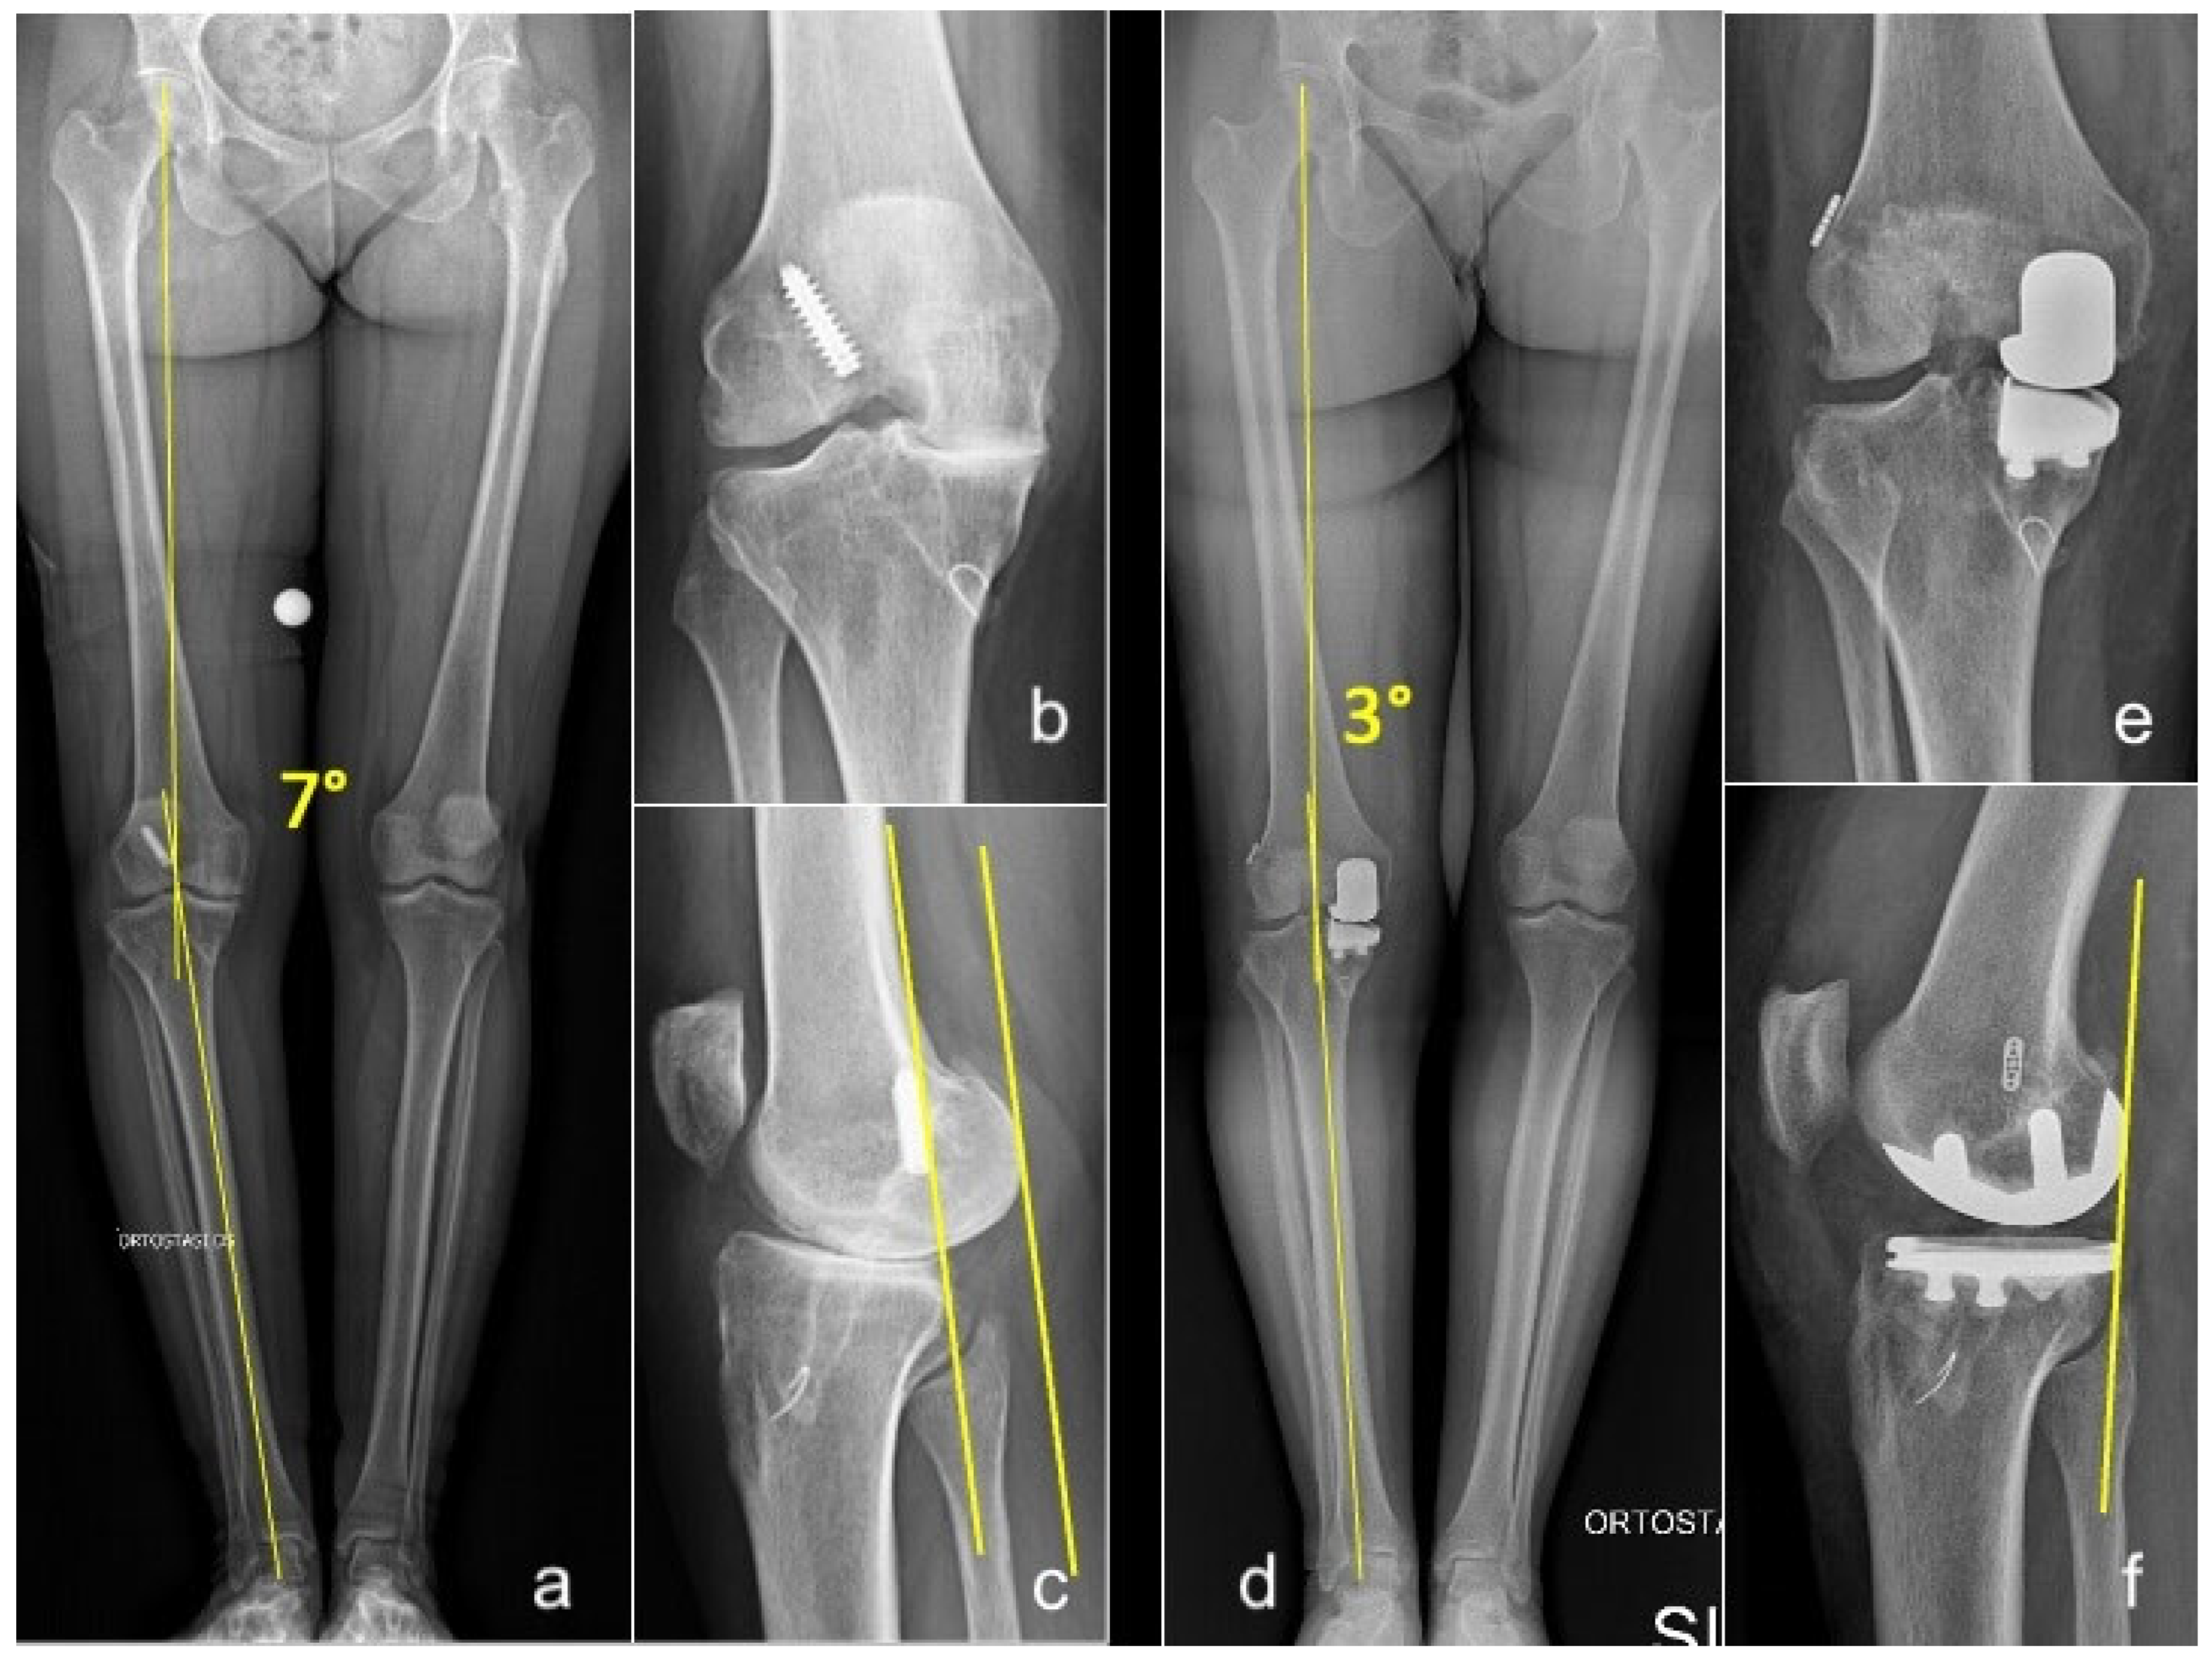

Figure 2. Long-standing whole-leg (a), anteroposterior (b), and lateral (c) radiographs of a 54-year-old female who presented with grade 4 medial OA and failure of a previous ACLR. Postoperative long-standing whole-leg (d), anteroposterior (e), and lateral (f) views after simultaneous medial UKA + revision of ACLR. Yellow lines in (a,d): hip-knee-ankle angle (HKA). Yellow lines in figure (c,f): posterior translation of the femoral condyles consequent to ACL deficiency, corrected after UKA+ACLR.

In open ACLR, UKA was performed first to correct the coronal deformity before placing the ACL graft. After trial reduction in the UKA, the femoral tunnel was created via the arthrotomy, and a guiding wire was passed through it. Then the UKA was cemented and, subsequently, the tibial tunnel was created to prevent cement invasion. The graft was then passed using the guiding wire and secured to the femur and tibia (Figure 2).

The following clinical scores were assessed during follow-up visits: the Knee Society Score (KSS) [24], both clinical and functional (KSS-C and KSS-F); the Tegner Activity Scale (TAS) [25]; and the University of California, Los Angeles (UCLA) Activity Score [26]. Laxity with anteroposterior (AP) translation was assessed clinically using the Lachman test at 30° knee flexion and compared to the contralateral knee. Routine weight-bearing anterior–posterior long-leg radiographs, Rosenberg view [27], true lateral view, and 30° patellar axial view radiographs were obtained preoperatively and at every follow-up visit. The hip–knee–ankle (HKA) angle was measured both pre- and postoperatively, defined by an angle formed by a line connecting the center of the femoral head to the center of the knee, and a second line from the center of the knee to the center of the talus. Varus alignment was defined as a mechanical axis less than 180°. Radiographs were assessed by two trained observers blinded to postoperative outcomes using a Picture Archiving and Communication System (Philips Medical Systems; Sectra-Imtec AB, Linköping, Sweden). All clinical and radiological assessments were independently conducted by two examiners (S.P. and F.B.) who were not involved in the surgical procedures.